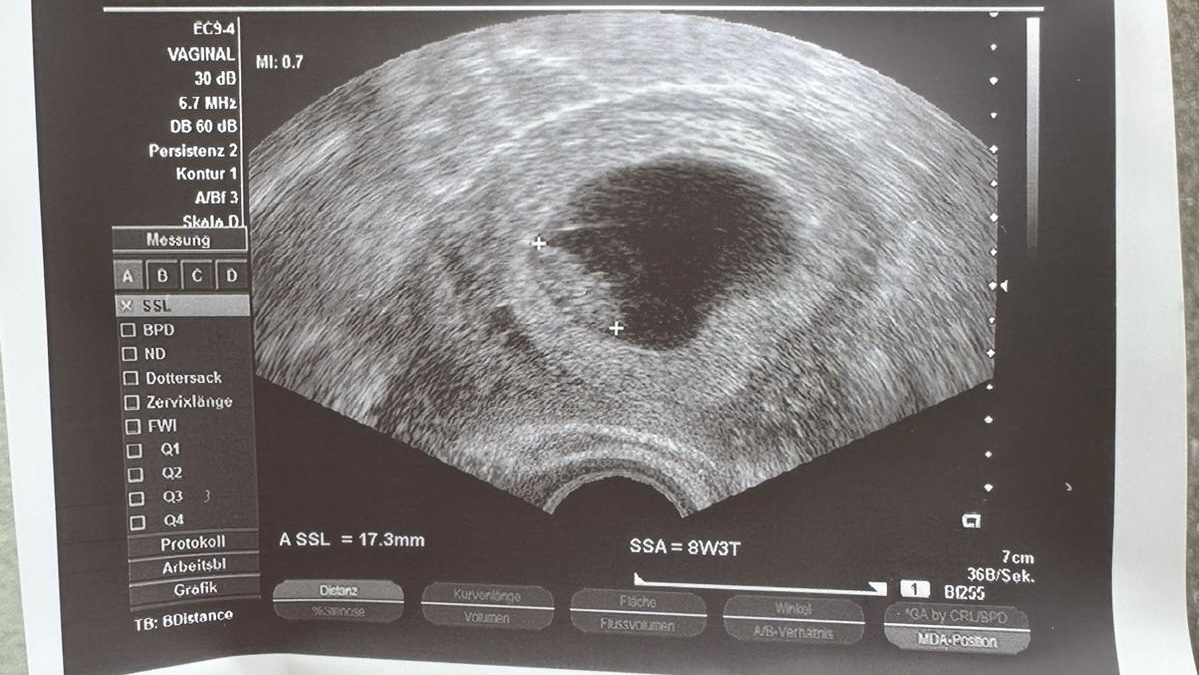

Cinsiyet tahminde bulunur musunuz

Konu Başlığı Cinsiyet tahminde bulunur musunuz